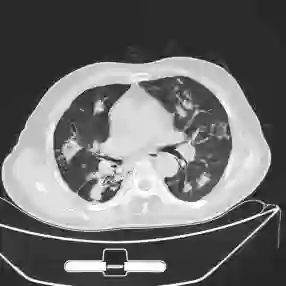

This paper proposes applying a novel deep-learning model, TBDLNet, to recognize CT images to classify multidrug-resistant and drug-sensitive tuberculosis automatically. The pre-trained ResNet50 is selected to extract features. Three randomized neural networks are used to alleviate the overfitting problem. The ensemble of three RNNs is applied to boost the robustness via majority voting. The proposed model is evaluated by five-fold cross-validation. Five indexes are selected in this paper, which are accuracy, sensitivity, precision, F1-score, and specificity. The TBDLNet achieves 0.9822 accuracy, 0.9815 specificity, 0.9823 precision, 0.9829 sensitivity, and 0.9826 F1-score, respectively. The TBDLNet is suitable for classifying multidrug-resistant tuberculosis and drug-sensitive tuberculosis. It can detect multidrug-resistant pulmonary tuberculosis as early as possible, which helps to adjust the treatment plan in time and improve the treatment effect.